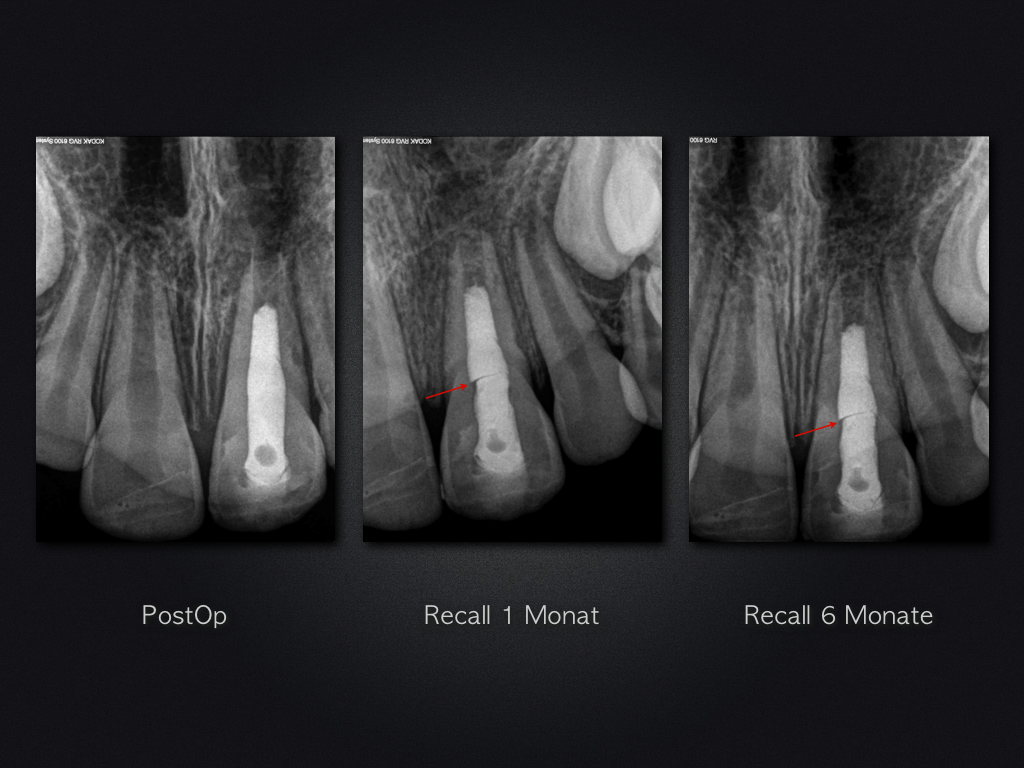

Revitalisierung – Recall nach 5,5 Jahren